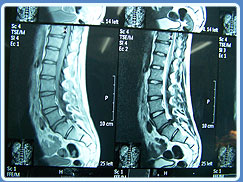

• Resonancia Magnética Nuclear

14. Tratamientos por padecimiento lumbares dolorosos de todos los tipos, como aquello por cirugía fallida de espalda, neurapatía del esfenopalatino, neuropatía diabética, neuralgia del trigémino, neuropatia del glosofaringeo; canal lumbar estrecho, síndromes facetarios, neuralgias postherpeticas, lumbalgias crónicas, Artrosis, Artrosis vertebral, degeneraciones osteotendinosas, discales con medicina biológica y homotoxicología, etc.

En procesos compresivos por radiculopatias el tratamiento de las Hernias Discales sin Cirugía con la utilizacion de la Ozonoterapia Intradiscales como las Paravertebrales por la vía percutaneas bajo control Fluroscopico o tomografico continuo y en serie, para tener una mejor eficacia del tratamiento intervencionista, en el lugar calificado, con las normas y con la ayuda de la Ozonoterapia intradiscales, dósis única o la vía paravertebral en 10 a 20 aplicaciones. Con ello se logra una disminución de la oxidación ( disminución del estrés oxidativo, como de sustancias irritativas anóxicas). Tratamiento de hernia de discos en una sola aplicación de Ozonoterapia bajo control flouroscópico, éxito 99% garantizado sin cirugía. Leer más Sobre Ozonoterapia, especialista en estudio y tratamiento del dolor en niños y adultos en dolores oncológicos y no oncológicos, dolor neuropático, neuralgia del trigénimo, neuralgia postherpética, nerupatía diabética, cefaleas, articualciones, lumbalgias y ciática, bloqueos simpáticos, simpatectomías químicas y térmica con equipo de radiofrecuencias, analgesia postoperatoria sin dolor, ozonoterapia en dolor por enfermedades crónicas en dolores articulares, hernias de disco vertebral, enfermedades inmunológicas, pie diabético infectado, psoriasis, infecciones de tejidos blandos, enfermedades crónicas, úlceras crónicas, varices, hemorroide crónica, Flebología y Medicina Hperbárica, Neuropatías, Radiocolopatías, Neuritis, Migrañas, Cefalea, dolor en Cáncer, Mucositis, Radioneuritis, dolor por Metastasis con paliación y modulación del dolor (cuidados paliativos y la Clínica del Dolor).